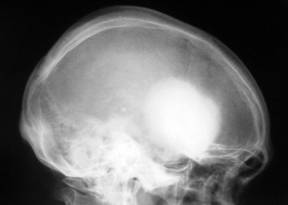

Aspectul radiologic

La nivelul craniului se evidentiaza zone de osteoliza rodunde de dimensiuni variabile în jur de 10mm cu contur net aratând ca niste gauri facute cu burghiul.